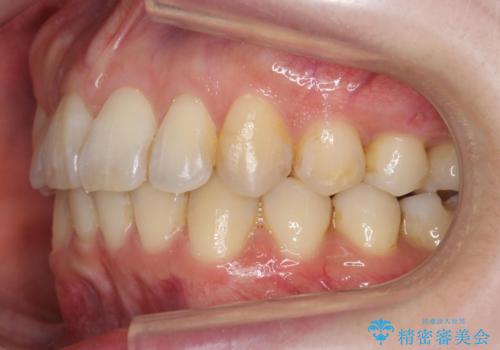

右下の臼歯が内側に倒れこみ、小臼歯部分はすれ違い咬合、大臼歯も反対咬合となっていました。

歯の大きさを計測したところ、下の歯がとても大きく、4本抜歯したとしても奥歯のかみ合わせを交互にするのが難しい状態でした。

この状態からうまく治療ができれば右下を頬側に起こすことができればある程度スペースが確保できそうでした。